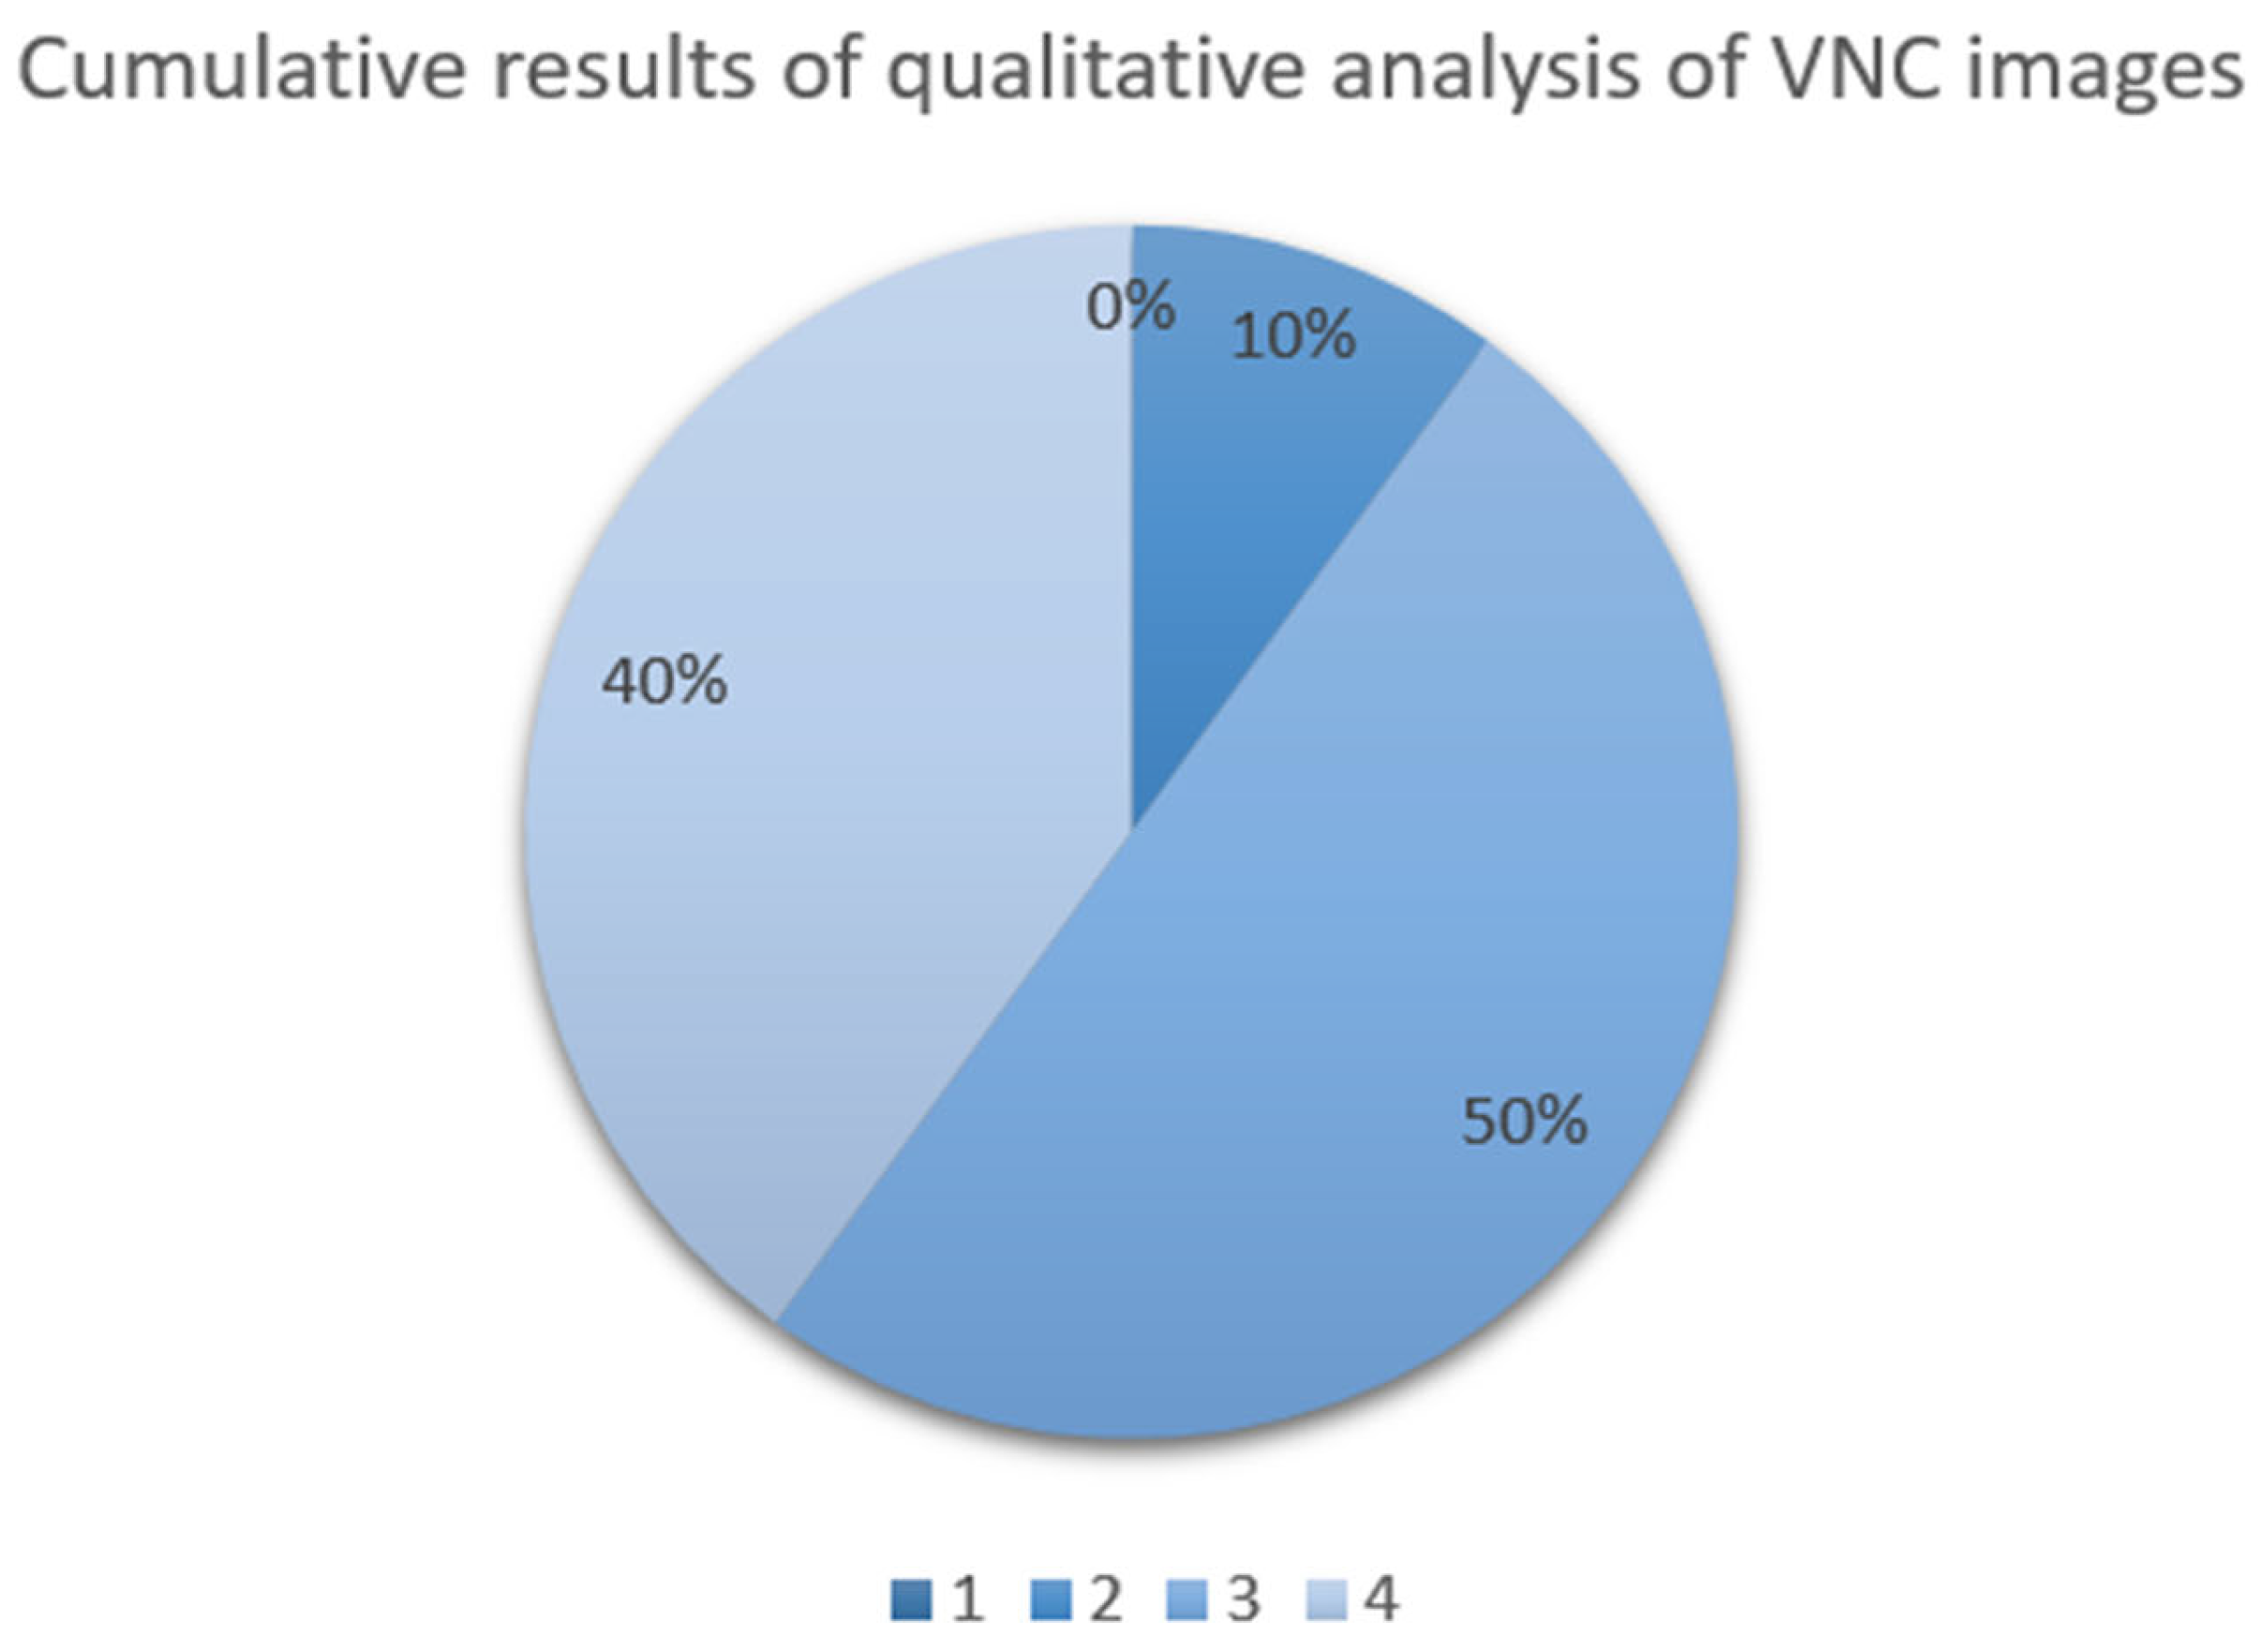

2.4. Image Analysis

3. Results

4. Discussion